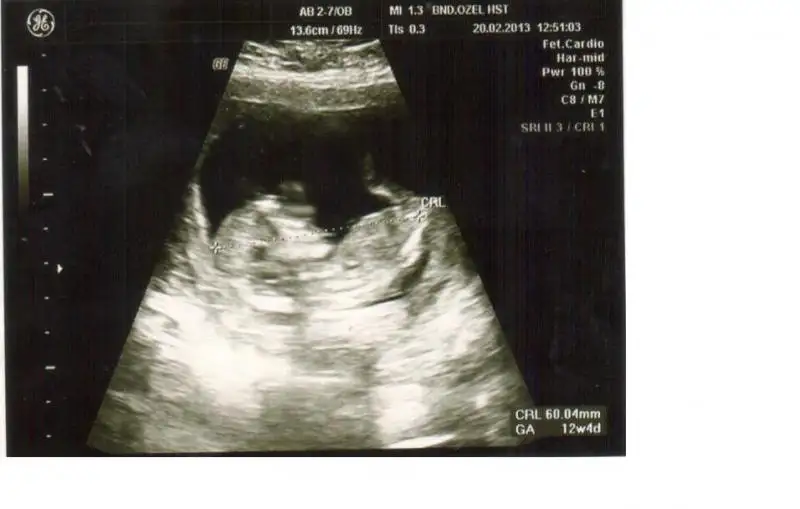

dr soylemeden siz gorun genital nub teorisi ( bebegin cinsiyeti)

dayanamadım,kızlar bende yorum bekliyorum sizlerden.ilk resim 11 hafta 3 günlük dr.erkek olcak dedi.ben pek inanmadım. 2.resim13 hafta 3 günlük,dr.muz bütün hislerim erkek olcakmış diyor dedi,yine inanmadım nedense.çok erken diye belki.yada kıza çok alışkınım hep içimden bir prensesim olacakmış gibi geliyor.4 yaşında dünya güzeli pirensesim var.rabbim hayırlısını nasip etsin.banada birrr yorum sevgili arkadaşlarım.bu işin ehli olmuş orkidem arkadaşım,senden de yorum bekliyorum.tabi musait olduğunda.....